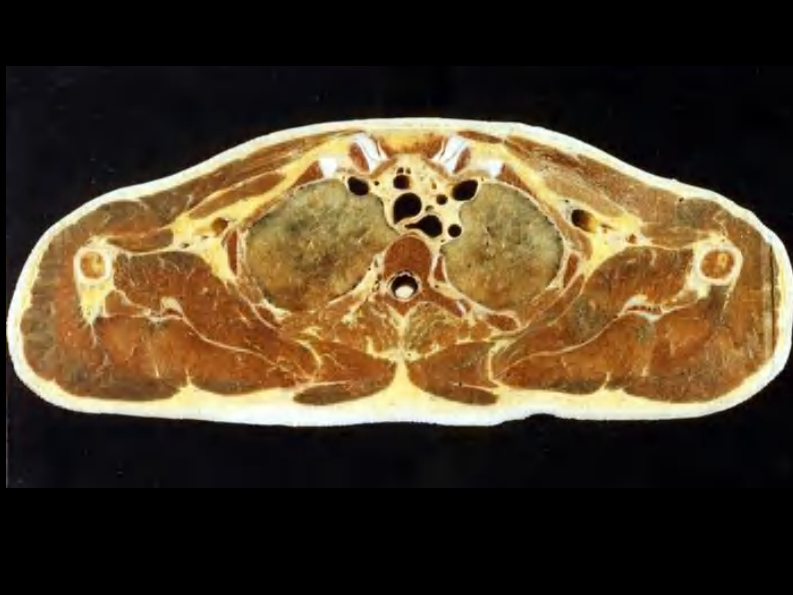

07 纵隔连续横断层解剖及CT.pdf